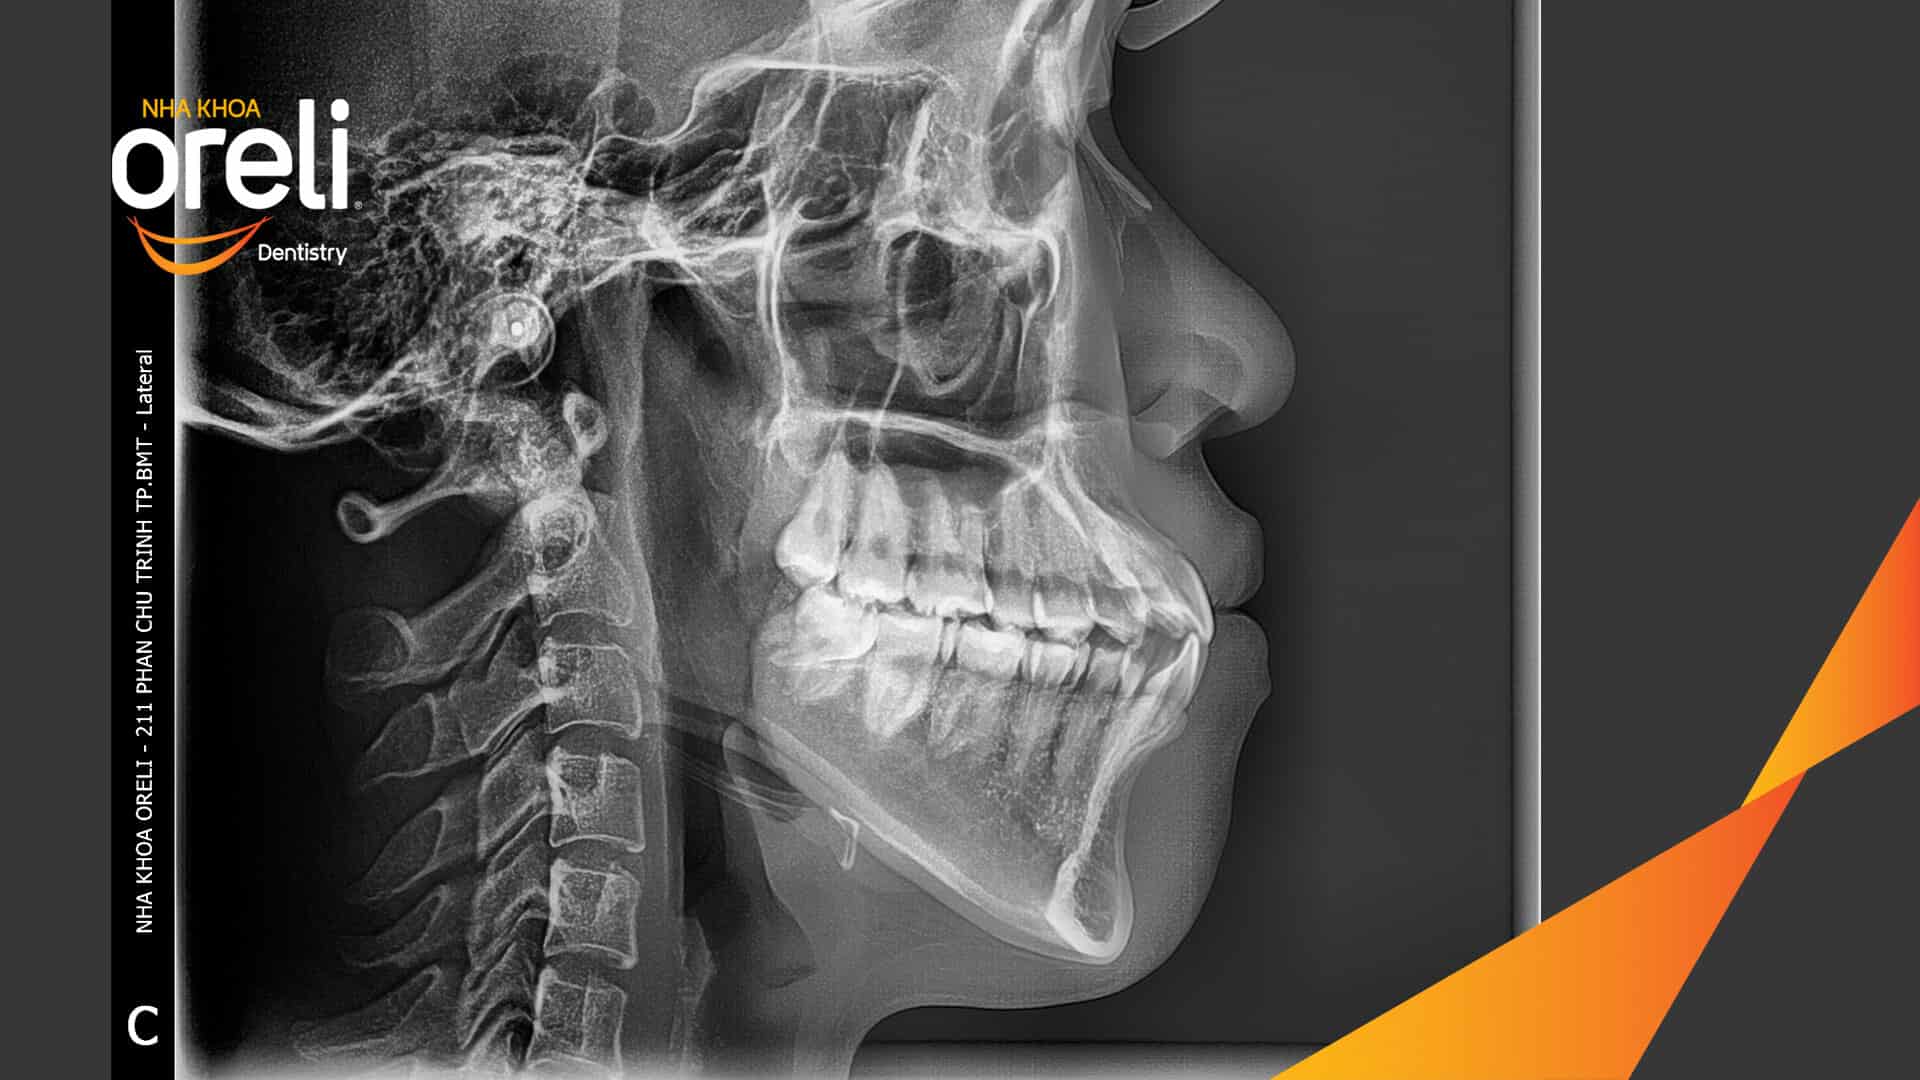

Hành trình thay đổi nụ cười ca lệch khớp cắn hạng 3, hàm dưới trượt ra trước và nhô xương hai hàm.

Tình trạng này không chỉ ảnh hưởng đến thẩm mỹ khuôn mặt mà còn gây khó khăn trong ăn nhai và phát âm. Thông qua quá trình niềng răng được cá nhân hóa, khách hàng đã từng bước cải thiện khớp cắn và lấy lại sự tự tin trong giao tiếp.